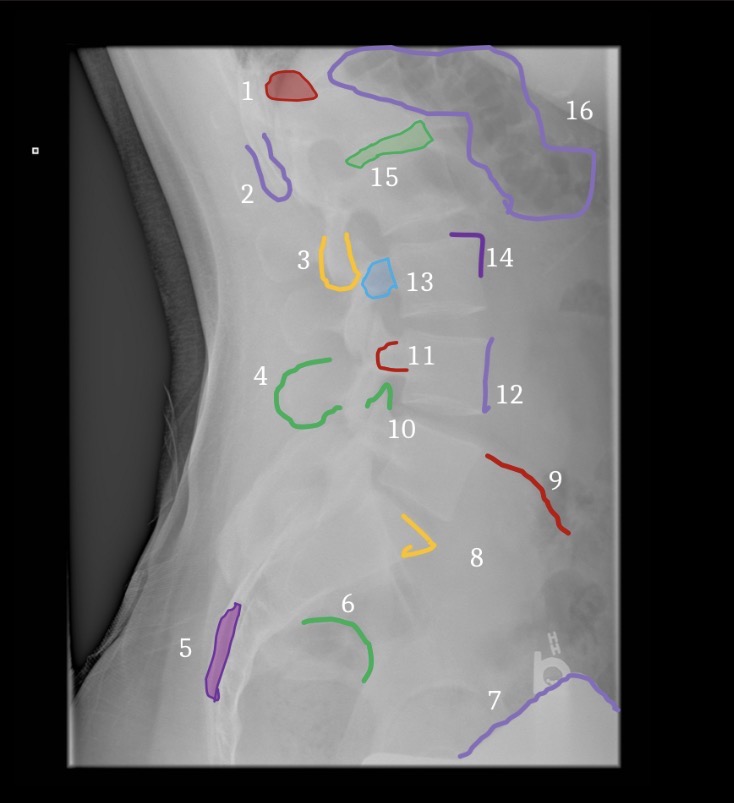

1

T12-L1 intervertebral foramen

2

Rib 12

3

Inferior articular process L2

6

Greater sciatic notch

5

Sacral canal

8

Sacral promontory

9

Iliac crest (2)

11

Transverse process L4

10

Superior articular process L5

12

Anterior body margin of L4

14

Anteriorsuperior body corner L3

15

Intervertebral disc space L1-2